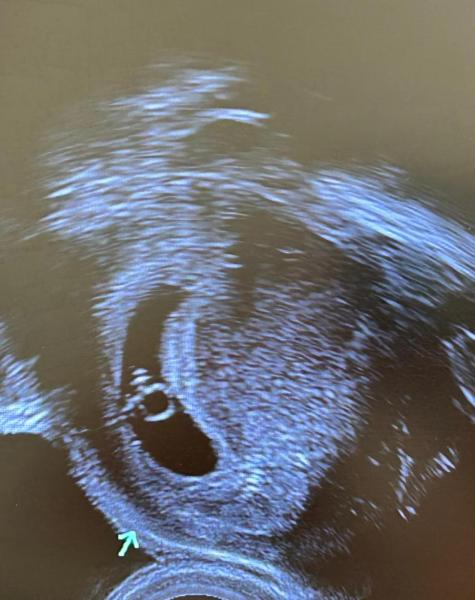

ich hoffe, es geht euch gut! Ich bin ganz neu hier umd momentan in der aufregenden Phase meiner Schwangerschaft. Ich habe heute mein erstes Ultraschallbild erhalten. Ich bin bei 6+0 und es wurde ein winziges Embryo sichtbar, aber leider konnte man den Herzschlag noch nicht wirklich erkennen. Mein Frauenarzt sagt es sei aber gut entwickelt und es schaut alles super aus. Er hat mir nun für nächste Woche einen weiteren Termin gegeben.

Huhu, du warst einfach ein, zwei Tage zu früh dort. Erst ab der 7. SSW (6+1) macht es Sinn, zum Arzt zu gehen, besser sind sogar noch ein paar Tage mehr. Das weißt man aber meistens erst ab dem zweiten Kind, beim ersten Mal rennen die allermeisten Frauen viel zu früh in die Praxis, das ging mir auch so. Ich drücke die Daumen, dass beim nächsten Mal ein Herzschlag zu sehen ist (wird bestimmt!). LG und eine schöne Kugelzeit!